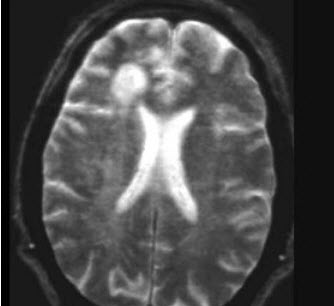

患者,一年前因轻截瘫诊断急性脊髓炎住院治疗,2周后基本痊愈;近10天来感觉四肢发紧、阵发性强直伴剧烈疼痛,入院时查头部MRI及BAEP、SEP和VEP均正常。对确诊多发性硬化最有价值的是( )

A:发现有感觉障碍平面

B:Lhermitte征(+)

C:CSF-IgG指数增高和寡克隆IgG带(+)

D:脊髓MRI检查

E:以上均不能确诊